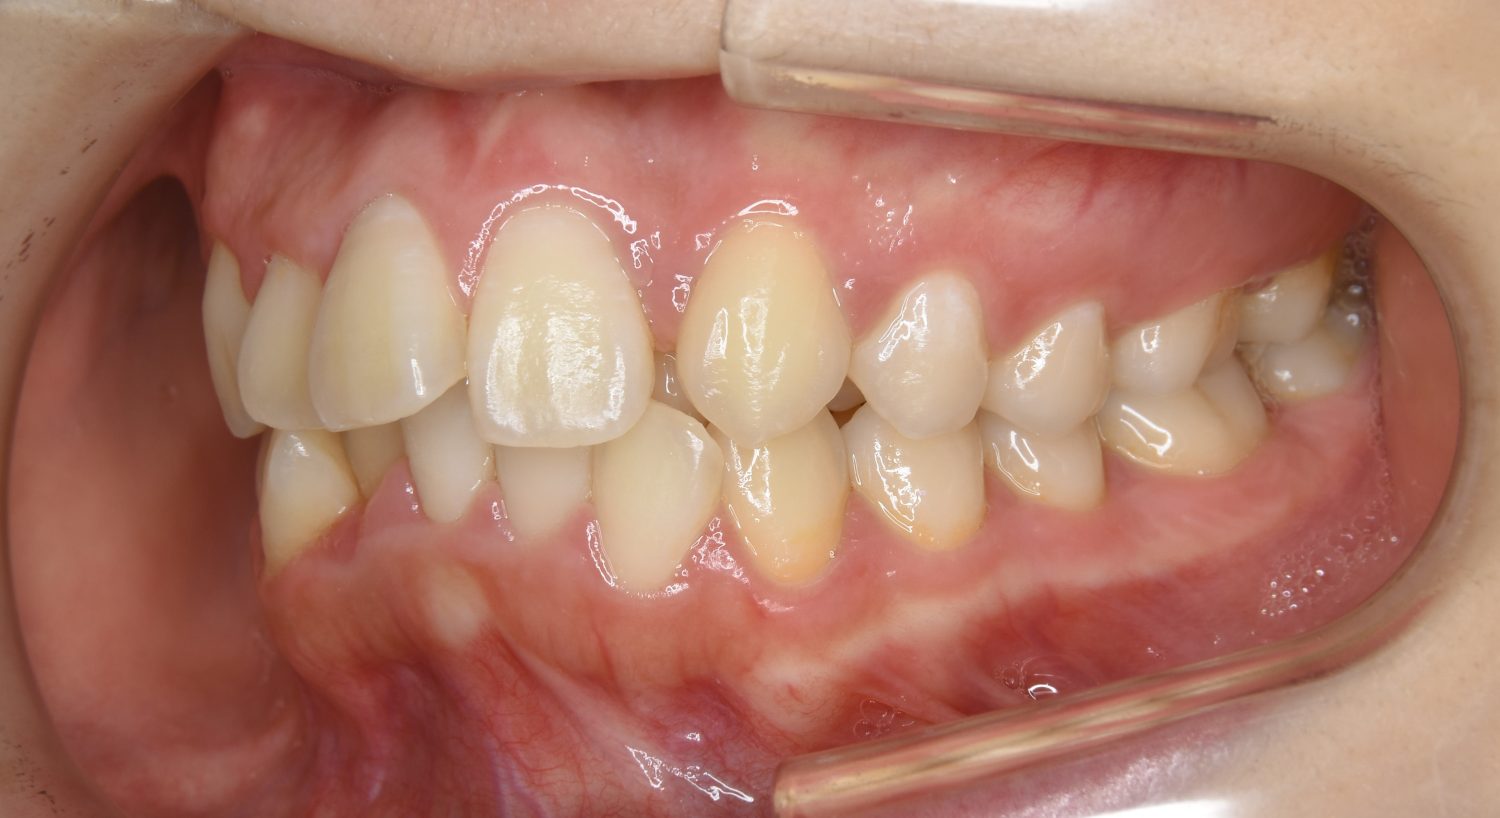

叢生の症例紹介②

Before

After

主訴

歯の凸凹を治したい。

治療内容

アライナー(インビザライン)にて非抜歯で治療を行いました。

上下前歯部に叢生(凸凹)が認められる状態でした。歯列の遠心移動を行うことで機能面および審美面が改善されました。